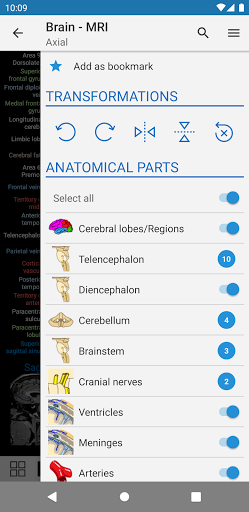

- Seleccione las etiquetas anatómicas por categoría

- Ahora puede ocultar las estructuras una por una (nuevo botón dentro de la ventana emergente de descripción) y visualizarlas nuevamente en el menú derecho